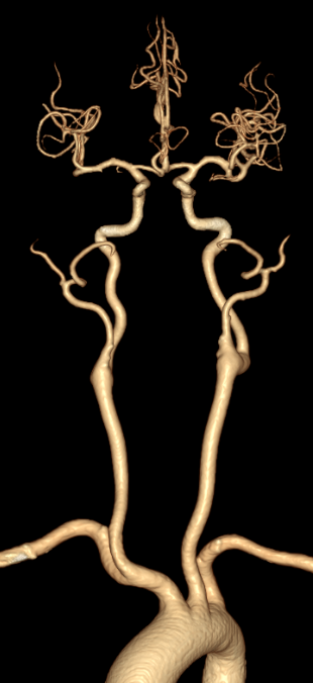

主动脉弓造影:主动脉弓呈"Ⅰ"型弓,依次发出头臂干、左侧颈总动脉起及左侧锁骨下动脉,以上三支血管开口未见无明显狭窄、扩张及斑块形成,前向血流正常。

猪尾巴导管行全脑血管造影,可见双侧椎动脉V4段闭塞。

左侧椎动脉造影提示左侧椎动脉V4段闭塞;右侧锁骨下动脉造影提示右侧椎动脉纤细并V4段闭塞。

复查造影:左侧椎动脉、双侧大脑后动脉、小脑上动脉、小脑前下动脉显影正常。

➢3月后复查头颈部CTA

双侧颈总动脉、颈内外动脉及颅底动脉环(Willis环)显示良好,双侧颈内动脉颅内段、双侧大脑前、中、后动脉及分支血管通畅,血管形态、走行规则,管腔通畅,管壁光整,管腔未见明显异常瘤样扩张、狭窄或闭塞。